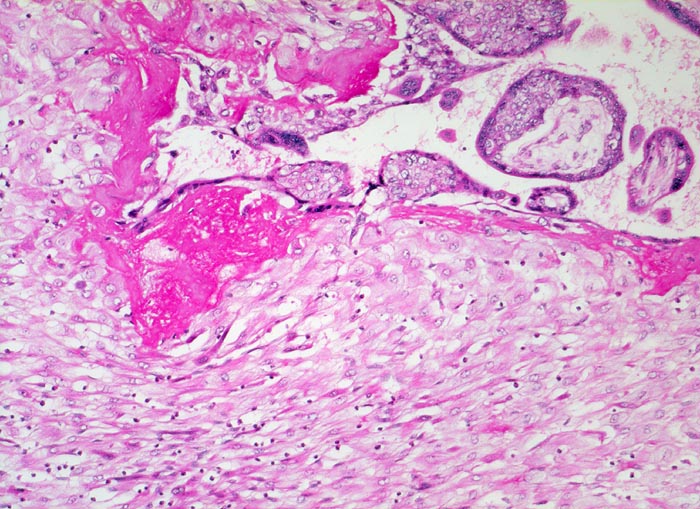

Gravidität: Haftzotten

Normalbefund

Plazenta

Unten im Bild die hellen zytoplasmareichen Deziduazellen mit vesikulären Kernen.

Fibrinoidschicht an der Deziduaoberfläche.

Kernknospe.

11. Schwangerschaftswoche. Normale Schwangerschaft